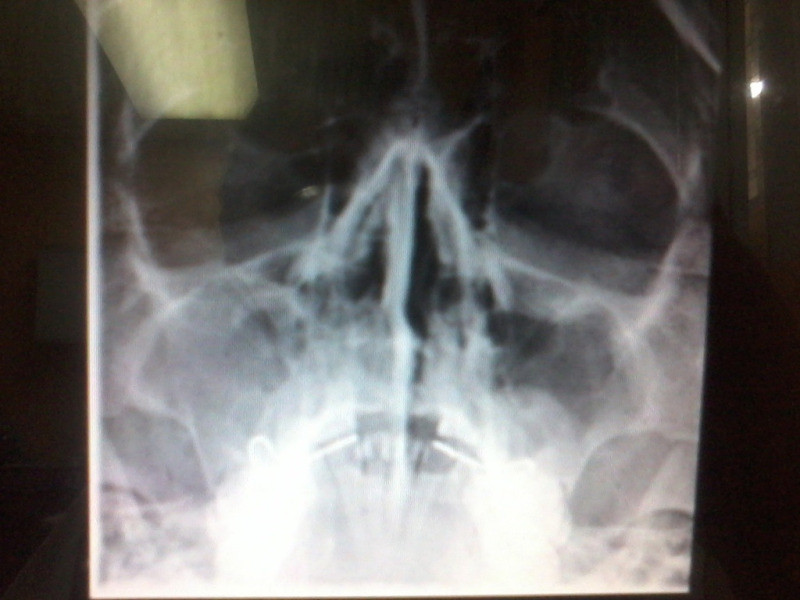

Sinusitis Crónica Desviación Septal Pólipo Maxilar Izquierdo